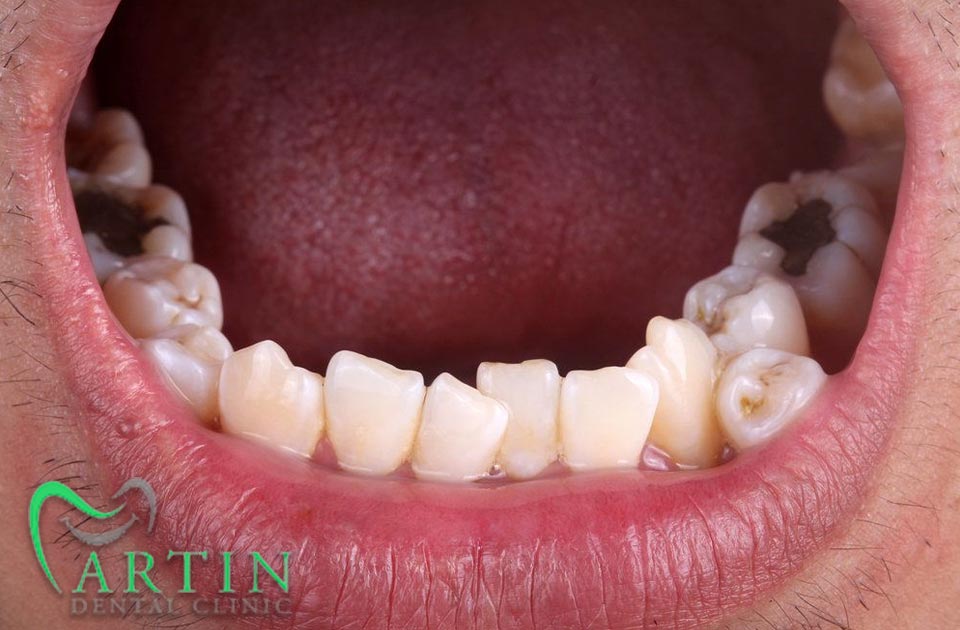

این نوع دندانها به طور طبیعی در دهان رشد میکنند و ممکن است در هر قسمتی از فک قرار بگیرند. این نوع دندانها میتوانند به شکل های مختلفی مانند دندان های اضافی در فک بالا یا پایین ظاهر شوند و زیبایی لبخند شما را از شما بگیرند.

- وجود دندانهای اضافی در فک: این دندانها ممکن است به راحتی قابل مشاهده باشند یا ممکن است در عمق فک قرار داشته باشند.

- عدم توازن در دندانها: این وضعیت ممکن است باعث بروز مشکلات زیبایی و عدم توازن در دندانها گردد.